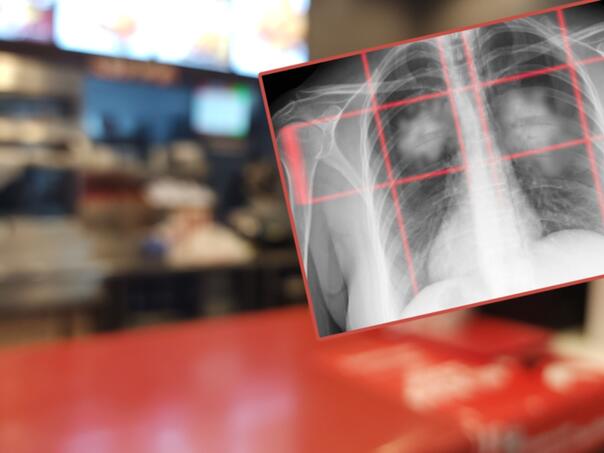

Novo istraživanje: Ultraprerađena hrana povećava rizik od raka pluća, čak i kod nepušača

Postoji još jedan ozbiljan razlog da izbjegavate ultraprerađenu hranu — novo istraživanje pokazuje da ona može povećati rizik od raka pluća. Ova vrsta hrane već je poznata po povezanosti s gojaznošću, dijabetesom i srčanim bolestima, a sada stručnjaci upozoravaju da može imati još teže posljedice po zdravlje.

Studija objavljena u časopisu Thorax analizirala je podatke više od 100.000 ljudi i otkrila da osobe koje najviše konzumiraju ultraprerađenu hranu imaju 41% veći rizik od razvoja raka pluća, čak i kada se uzmu u obzir faktori poput pušenja. Istraživanje je pokazalo da je veza bila još izraženija kod nepušača.